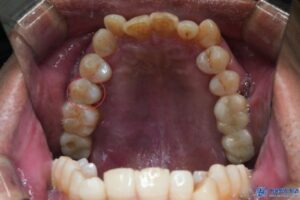

위 환자분은 50대 중반의 남성분으로,

오른쪽 위, 아래 어금니 잇몸이 많이 붓고

흔들림과 통증이 있다고 하셨습니다.

진단 결과, 상악 우측 작은 어금니와

하악 우측 큰 어금니 2개 부위에

만성복합염증이 광범위하게 퍼져 있었고,

염증으로 인해 뼈도 많이

손실된 상태였습니다.

이로 인해 세 치아 모두 흔들림이 심했고,

보존하기 어려운 상태였기에

발치 후 임플란트를 결정하였습니다.